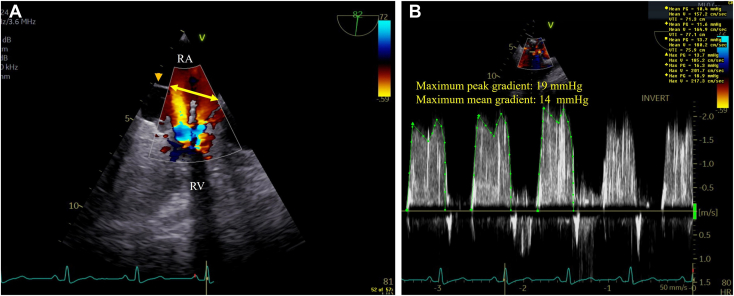

In addition, 2D TEE with color-flow Doppler demonstrated the nonobstructive dividing RA membrane with a large (2.0 cm) aperture with nonturbulent flow at this level in contrast to turbulent flow at the TV inflow level caused by the obstructive mass, which was further supported by maximum peak and mean gradients of 19 mm Hg and 14 mm Hg, respectively, by continuous-wave Doppler (Figure 5, Video 5).

Figure 5.

(A) Two-dimensional TEE, midesophageal right heart–oriented (82°) view with color-flow Doppler during late diastole, demonstrates the dividing RA membrane (arrowhead) with a large (2.0 cm) aperture (double-headed arrow) with nonturbulent flow at this level, in contrast to turbulent flow at the TV inflow level (arrows) caused by the obstructive mass. (B) Two-dimensional TEE, midesophageal right heart–oriented (82°) view with color-flow Doppler-guided continuous-wave Doppler, demonstrates severe TV inflow obstruction with maximum peak and mean gradients of 19 mm Hg and 14 mm Hg, respectively (at a heart rate of 80 bpm). RV, Right ventricle.